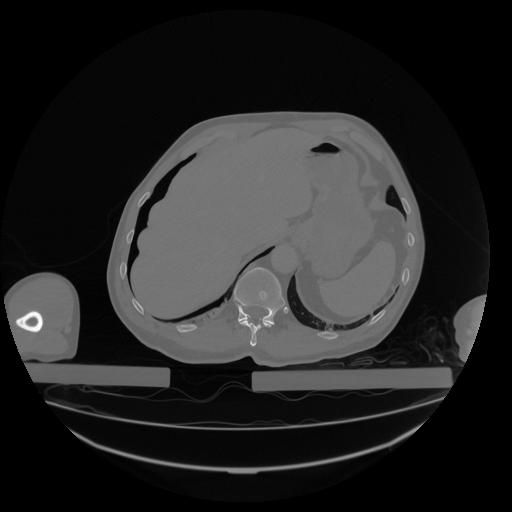

34 CUERPO,CE,Vol,1.0,CUERPO,,